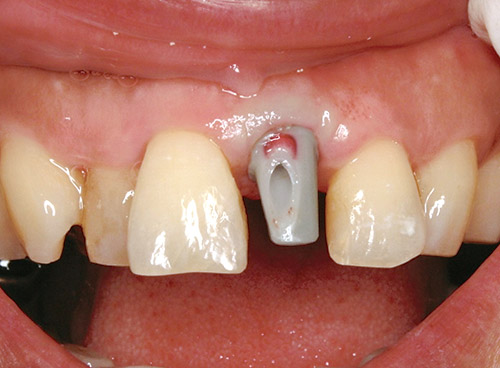

粘膜をパンチアウトし、SIQ値に問題がなければ、テンポラリークラウンを作製していくのだが、SPIのテンポラリーアバットメントは大変操作性に優れている。

私は、大臼歯部や小臼歯部においてはジンジバルフォーマーのみでティッシュスカルプティングを行うこともあるが、前歯部においては必ずチェアサイドでテンポラリーアバットメントの調整を行うようにしている。その際、気を付けていることは、遊離歯肉状態になっている歯肉に対して圧を決してかけすぎないようにすることである。

さらに、気を付けていることは、1歯欠損の場合、反対側同名歯のマージンの位置よりも1mm弱程度歯肉が高い状態で歯肉を安定させておくことである。

図15 カスタムアバットメントのワックス試適。歯冠回復をして想定する形態をおこしてからワックスミリングをしている。隣在歯との歯頸ラインに特に注意をしている。 -

図16 カスタムアバットメントのワックス試適(咬合面観)。 -